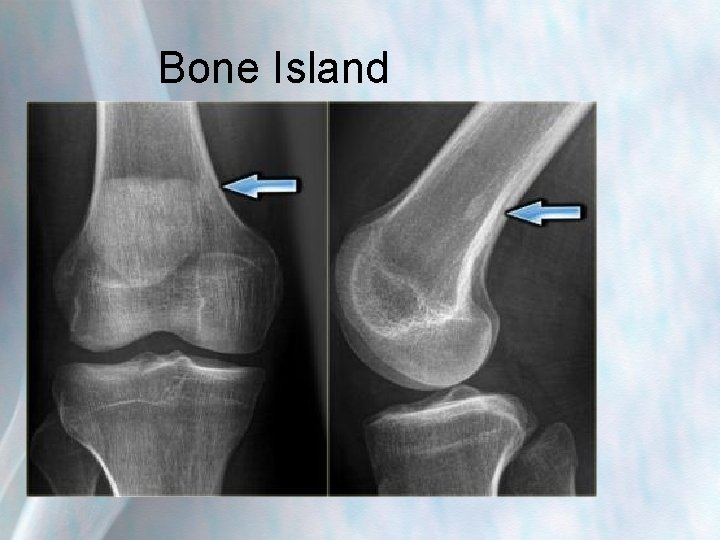

Bone Island

Bone island (enostosis) • Benign bone tumour normally pain free-rarely requires treatment • Difficult to distinguish radiologically from an osteoid osteoma, osteoblastoma (benign but often require treatment) and low grade osteosarcoma (malignant)more suspicious in history of malignancy • Normally grow within medullary canal of bone • Typically sclerotic, round-to-ovoid intramedullary foci. The long axis of the bone island is aligned parallel to the long axis of the bone. • Composed of cortical bone, so demonstrate low signal intensity on all sequences of MRI scans.